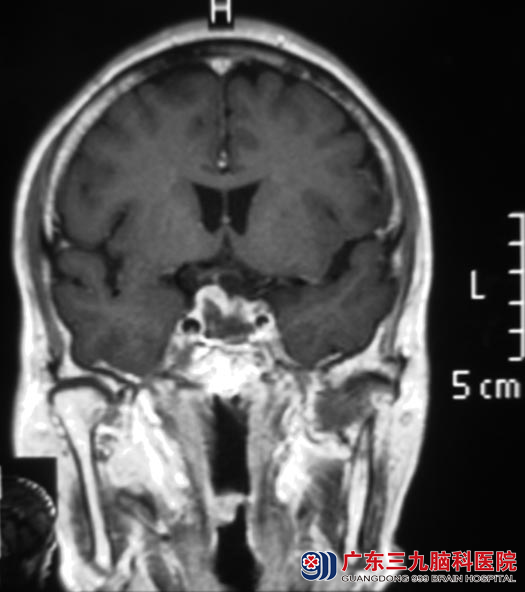

两天后,陈爷爷在全麻下接受了经鼻蝶垂体瘤切除术,术前导航定位,术中可见肿瘤呈灰白色,质软,易吸出,包膜完整,镜下近全切除肿瘤,鞍膈下陷,无脑脊液流出。术后第二天,他的视力较前好转,没有出现并发症。术后病理结果为:垂体瘤(泌乳素型垂体腺瘤)。

▲手术后